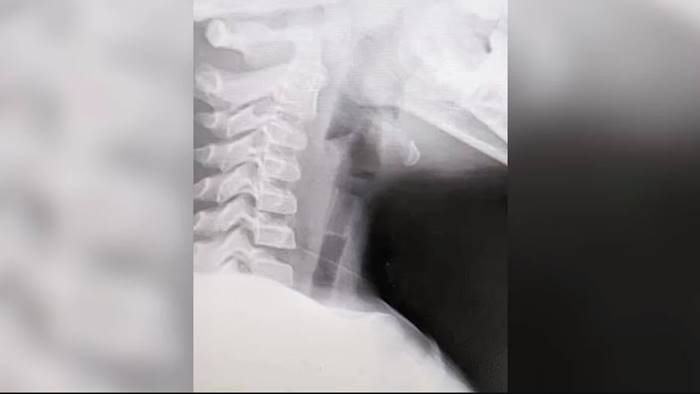

แพทย์หญิงกฤษณพร จิรวรากุล แพทย์องค์กรแพทย์ หู ตา คอ จมูก โรงพยาบาลยะลา เปิดเผยว่า กรณีดังกล่าวถือว่าโชคดี เพราะนกหวีดเป่าลมมีรู ทำให้มีช่องลมให้หายใจเข้า-ออกได้อยู่เพียงแต่จะมีเสียงดังเวลาหายใจเท่านั้น เพราะหากเป็นวัสดุที่ไม่มีรูจะเกิดอาการอุดตันร้อยเปอร์เซ็นต์ทำให้เด็กขาดอากาศหายใจอาจถึงขั้นเสียชีวิตได้ โดยหลังจากมาถึงโรงพยาบาลแพทย์ได้ทำการเอกซเรย์หาตำแหน่ง ก่อนวางยาสลบ เปิดกล่องเสียงเพื่อคีบไส้นกหวีดที่ติดอยู่ออกมาได้ปลอดภัยใช้เวลาประมาณ 15-20 นาที

จากการสอบถามครูที่อยู่ในเหตุการณ์เล่าให้หมอฟังว่า ขณะเกิดเหตุเด็กคนนี้มีอาการไออย่างรุนแรง จึงสงสัยว่าสำลักสิ่งแปลกปลอมเข้าไปโดยนกหวีดเมื่อตกผ่านสายเสียงแล้วได้หล่นไปในหลอดลม และค้างที่หลอดลมส่วนต้น ทำให้เมื่อเด็กหายใจเข้า-ออก จึงมีเสียงนกหวีดดังออกมา